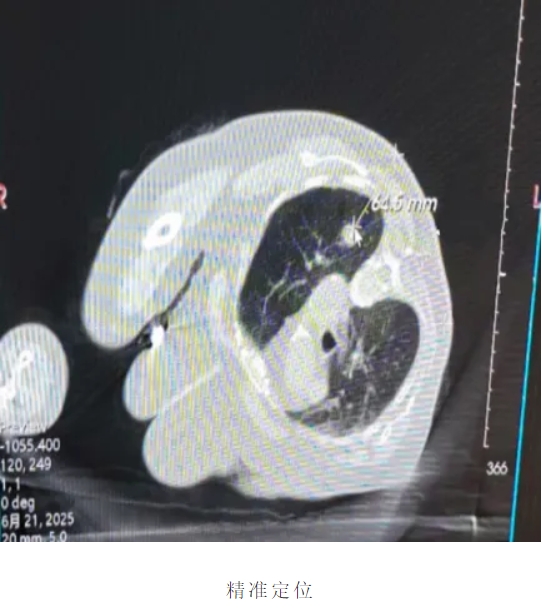

患者老年女性,既往高血压3级很高危、阑尾术后、胆囊结石术后,多种药物过敏史,病灶位于左肺上叶。面对患者高龄、合并多系统疾病等严峻挑战,我院胸外科团队与辽宁省人民医院胸外科专家杨海涛教授深入探讨治疗方案,与患者家属充分沟通后最终决定为患者行微波消融术,术中在CT引导下精准定位靶点。面对患者高龄、合并多系统疾病等严峻挑战,我院胸外科团队与杨海涛教授深入探讨治疗方案,与患者家属充分沟通后最终决定为患者行微波消融术,术中在CT引导下精准定位靶点。

患者老年男性,既往高血压3级、糖尿病、肺气肿,病灶位于右肺下叶。患者微波消融意愿强烈,通过团队积极讨论,在解决结节的同时为后期治疗提供有力依据,术中在CT引导下精准定位靶点,活检、消融一体化。同期解决患者痛点。